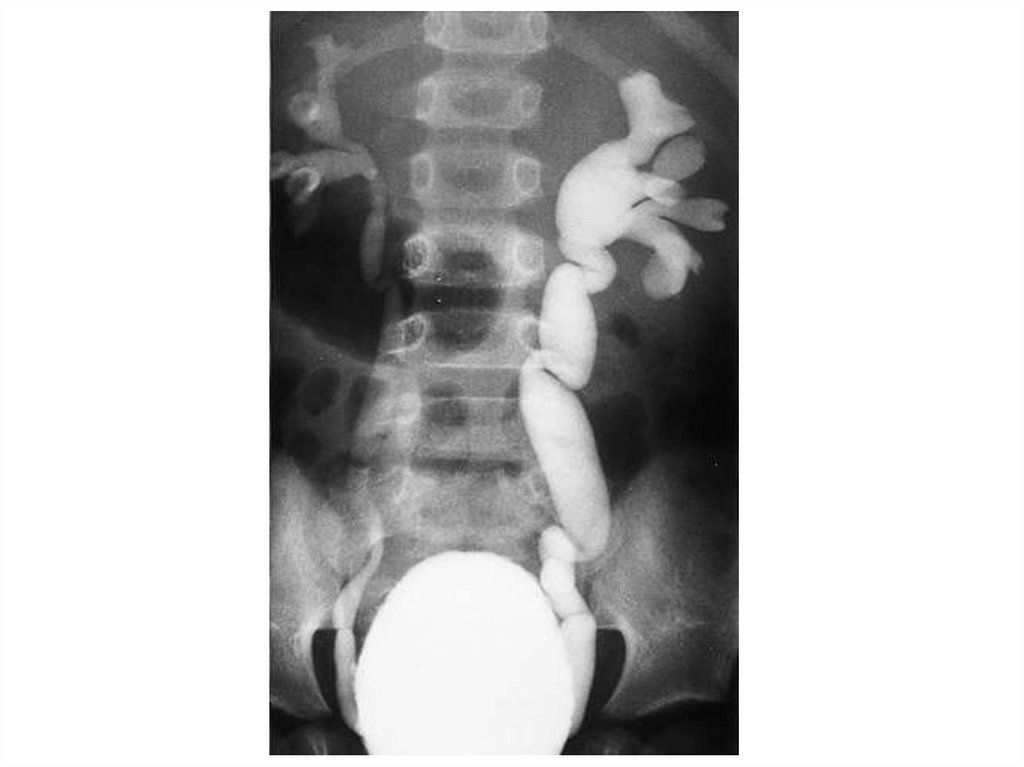

На рентгенограммах грудного и поясничного отделов позвоночника в

двух проекциях лёжа отклонение оси позвоночника влево на уровне Th4Th12, угол сколиоза 650 (4 степень сколиоза) с правосторонней

противодугой на уровне Th12-L4, угол сколиоза 450. Признаки

патологической ротации тел позвонков 4 степени. Грудной кифоз усилен

(угол кифоза 720). Вентральная клиновидность тел грудных позвонков на

высоте кифоза. Снижение высоты межпозвонковых дисков.